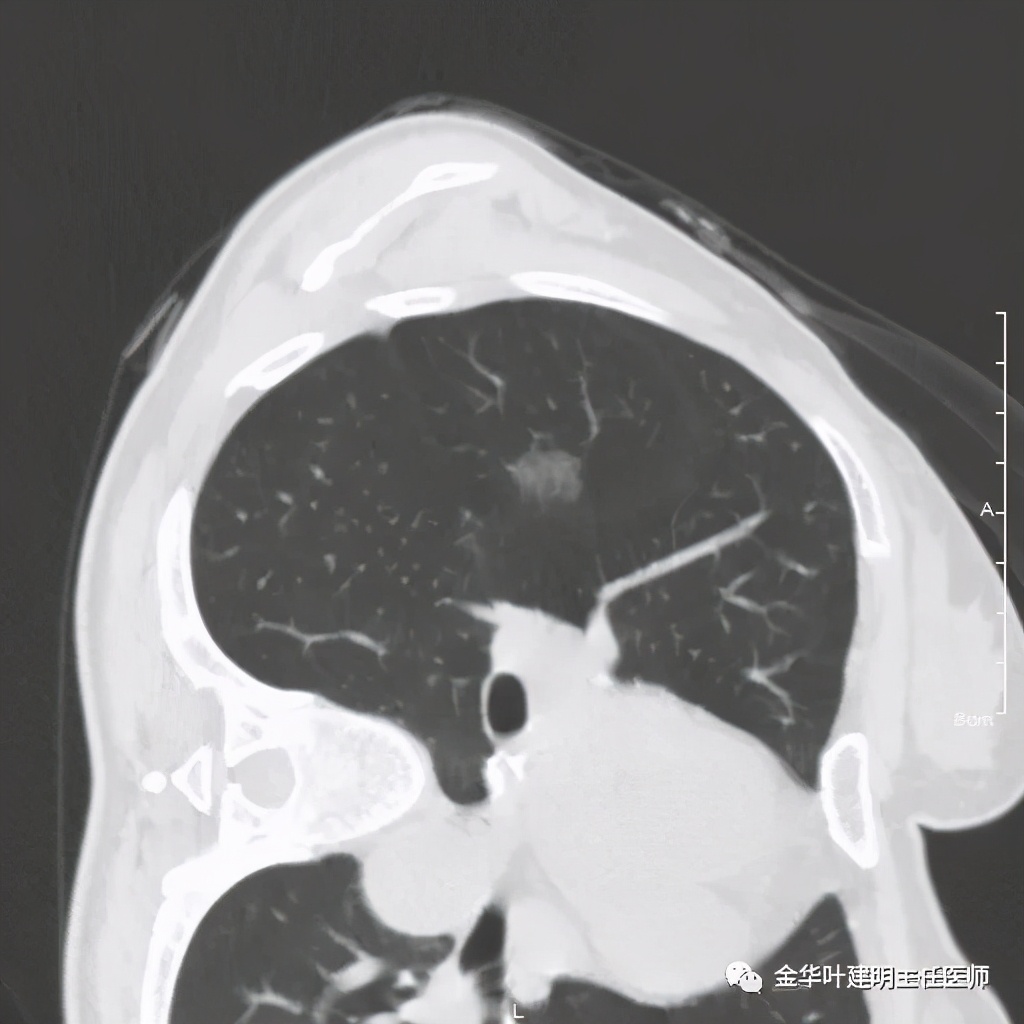

五、浸润性腺癌之粘液腺癌:

影像特征:这个病例是我在术前仅凭影像就判断其为粘液腺癌,术后确诊的。粘液腺癌表现为 实性乏收缩力、密度较均匀 的实性结节。病灶的边界一般非常清楚,没有毛刺、磨玻璃、卫星灶等,但又乏收缩力,像本例紧贴胸膜也不会有牵拉凹陷;同时病灶的密度又比较均匀(粘液成份)。良性肿瘤密度要更高些、慢性炎没有这么光整的边界,也容易有瘢痕收缩方面的影像表现、其他实性的腺癌则要有收缩力、腺泡型虽然也缺乏收缩力,但密度要不均匀些。